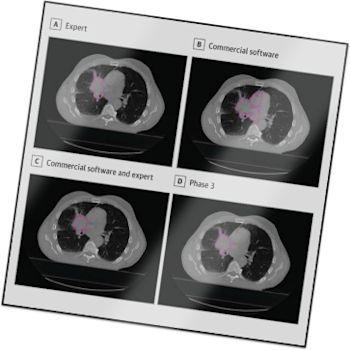

Manual tumor delineation—the measure of treatment field borders of tumors—is a time-consuming and complicated process. Among other pain points, it introduces individual bias as well as person-to-person inconsistencies. Topcoder joined forces with Harvard to tackle one of the most ambitious healthcare initiatives ever undertaken in the crowdsourcing world—creating and testing automatic delineation algorithms to help improve treatments of cancerous tumors in patients’ lungs.

The Topcoder Harvard Tumor Hunt aimed to produce an automatic tumor delineation algorithm that met the accuracy of the average radiology expert but exceeded them in both processing speed and consistency.

These three challenges produced an algorithm that replicated the accuracy of an expert radiation oncologist in segmenting lung tumors for radiation therapy targeting. In fact, Topcoder’s AI solution yielded a 9-12% boost in accuracy. The algorithm functioned as well — and in some cases, better — than a panel of radiation oncologists in segmenting lung tumors on patient CT scans, and it completed the task in mere seconds (ranging from 15 to 120). Human experts typically take between 10 and 30 minutes.